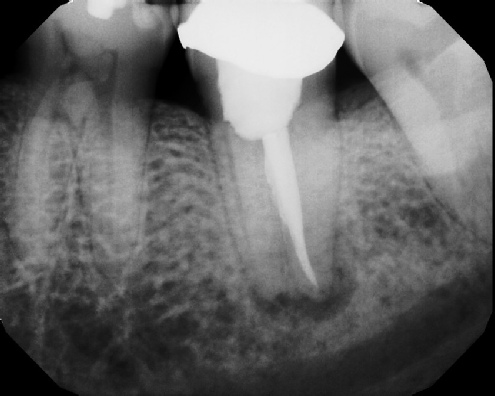

Root Canal Retreatment - Meriden 8 mos. recall Post-op Pre-op